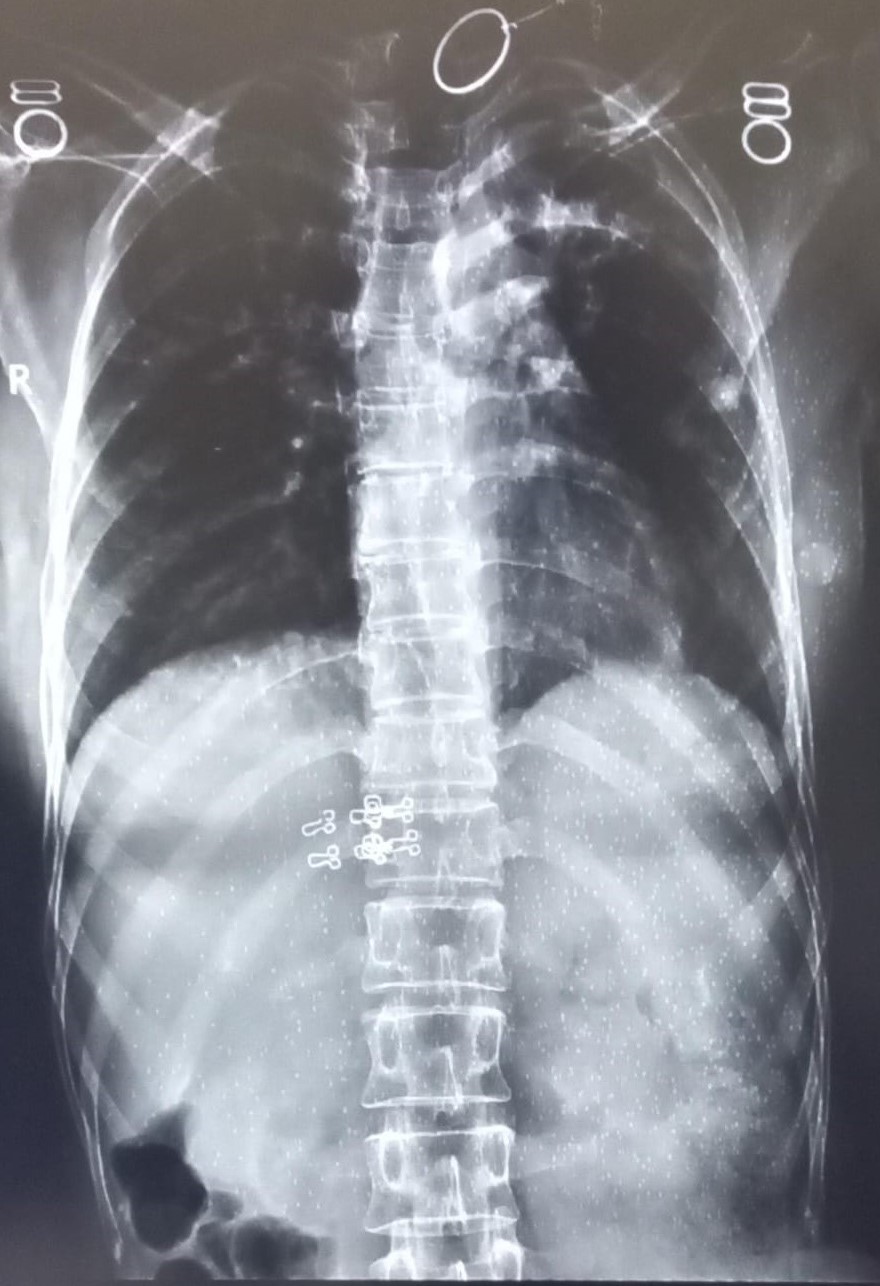

| 4440 | IGGMC, Nagpur, Nagpur | P2 | 29-32 | kamal dasar | Consent taken on Paper | 49 Yrs. |

Provisional Diag : cough under evaluation

Final Diag : OBLITERATION OF LEFT CP ANGLE BLUNTING/LEFT SIDED PLEURAL EFFUSION |

Non-TB Case (Confirmed) | OBLITERATION OF LEFT CP ANGLE BLUNTING/LEFT SIDED PLEURAL EFFUSION | Abnormality visible on x-ray |